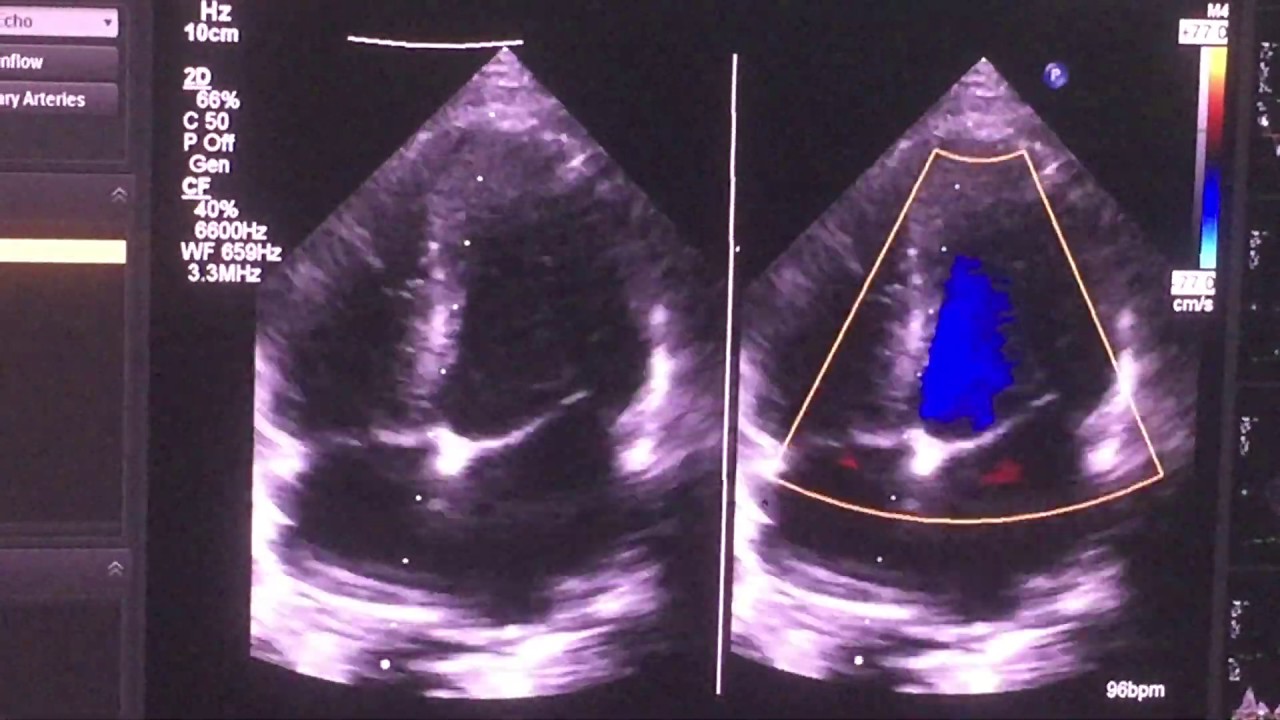

Mid muscular VSD скачать в хорошем качестве

Mid muscular VSD

Assalam 0 Alaikum viewers.. Interventricular septum is formed of four componants.Trabecular/muscular,inlet,outlet and membranous .Defect in any of these areas will be named accordingly. Muscular VSDs are usually small and rarely cause hemodynamical harm to the pt. On examination theses VSDs produces harsh systolic murmur so detected in early neonatal life. Majority of them closes spontaneously.